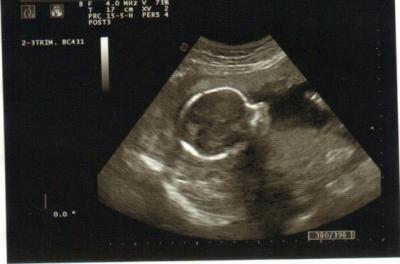

Der Zwerg und ich sind nun schon in der 30. Woche, was bedeutet, dass ich in diesem Jahr mehr schwanger als nicht schwanger war.

Der kleine Mann hingegen liegt noch immer sehr entspannt die optimale Raumverteilung nutzend in Querlage. Ich hoffe er dreht sich irgendwann nochmal.